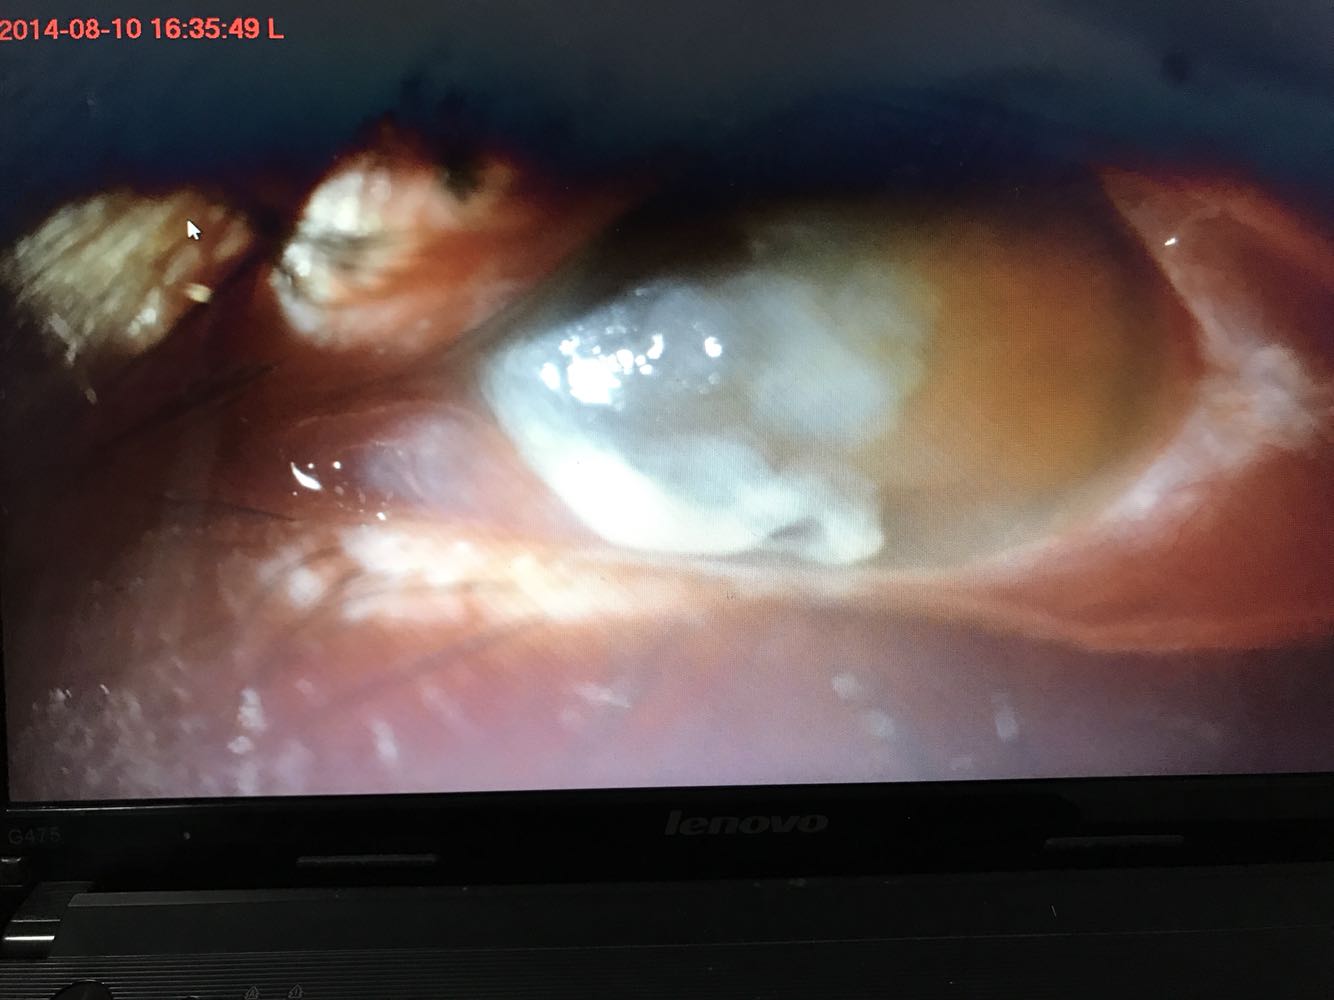

视力:右 1.0,左 眼前手动。左眼睑水肿痉挛,球结膜混合性充血+++,见大量脓性分泌物 。鼻侧角膜上皮部分脱落,基质弥漫性水肿。瞳孔大小可,对光反射迟钝,余窥不清。

这是治疗后的照片,视力0.1。